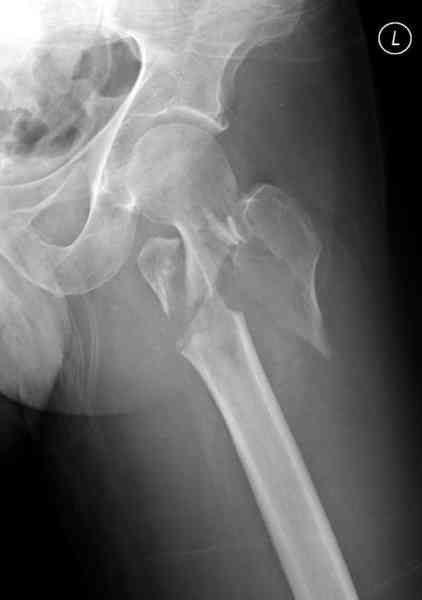

Применили проксимальную Synthes Locking plate, из-за множественных фрагментов посчитали более приемлемым в этом случае (клиника университетская, резиденты должны имет возможность созерцать разные варианты остеосинтеза).

Также старался минимизировать доступ на уровне перелома с субвастус доступом, диафиз фиксирован перкутанно, не стали гонятся за малым вертелом, как смог зафиксировал.

Перелом из четырех фрагментов, не стабильный (лекция Michael R. Baumgaertner, http://www.hwbf.org/ota/bfc/baumg/exp.htm), нужна стабильная фиксация.

Фиксация таких нестабильных чрезвертельных и reverse obliquity субтрохантерик переломов всегда была сложной задачей и ранее использовали Blade Plate. Но многие локальные общие ортопеды, к которым, в основном поступают такие больные, имели трудности с применением импланта, где необходимо было точная калькуляция по введению Blade и поэтому Synthes разработал Proximal Locking plate как альтернативу, где три проксимальные шурупа в разных направлениях создают концепцию угловой стабильности Blade Plate.